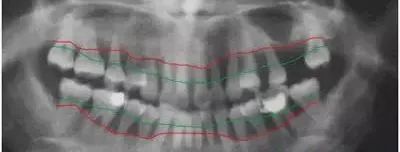

一位晚期牙周病患者的曲面断层片,绿线标示的是正常牙槽骨大概的位置,红线是这位病人牙槽骨实际的位置。(郑重声明:曲线如此并非手抖造成,一是牙周炎造成的牙槽骨吸收本来就不均匀,二是此病人牙齿略有不齐,正常的牙槽骨高度各部位也存在一定差异。)